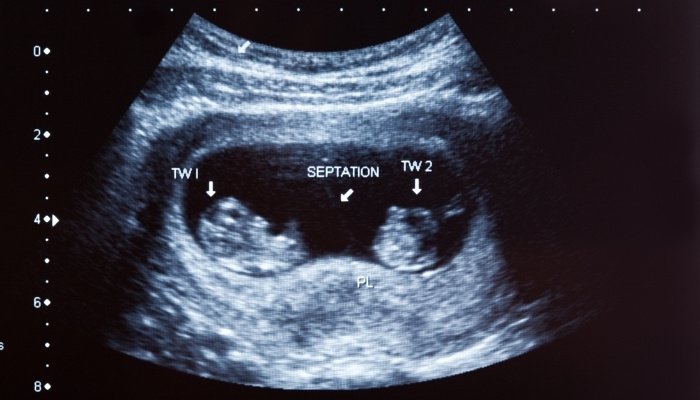

Ultrasound

Gender can be detected by ultrasound as early as 12 weeks. However, early ultrasound scans are not as accurate as later ones.

Given the increased probability of misgendering during this time, many sonographers will err on the side of caution and recommend waiting until a later scan.

At 14 weeks, prediction accuracy increases significantly because the genitals are fully developed. Gender determination via ultrasound occurs most often at the fetal anatomy scan around 18 to 20 weeks gestation.